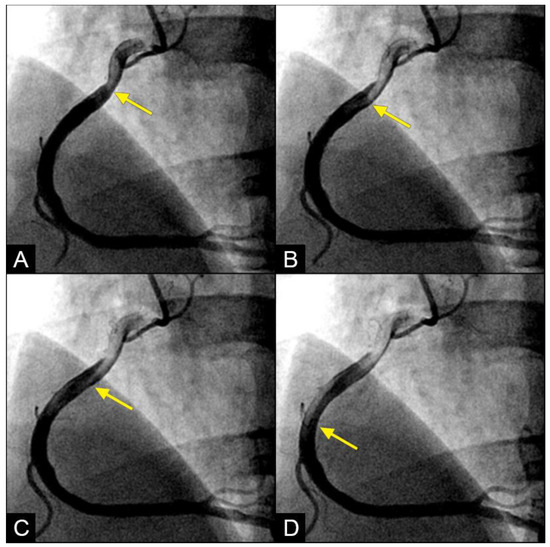

In the right coronary artery (RCA), with the novel angiographic technique, during diastole, the antegrade flow was clearly illustrated (Figure 9A–D). The leading edge of the flow was sharp, suggestive of laminar flow (Figure 9C). The speed in diastole was fast, as the blood could traverse from the end of the proximal segment to halfway through the mid-segment in just 0.067 s, equivalent to one image interval (Figure 9D). At this junction, at the onset of systole, the antegrade flow decelerated (yellow arrow), while the mixed black contrast persisted at the location of the transition from diastole to systole (red arrow). This contrast remained until near the end of systole, providing visual evidence of disorganized flow secondary to the interaction between the retrograde and antegrade flows; most likely, it was a collision (Figure 9E–H) (Video S2).

Figure 9.

(A–D) Collision in the RCA. This is a series of eight consecutive images of an angiogram of the right coronary artery (RCA). (A) The artery is filled with contrast. There is a moderate lesion at the mid-segment. (B) The blood (white) is seen entering the ostium of the RCA (arrow). This is the beginning of diastole. (C) The blood (white) is seen at the outer border of the first curve of the RCA (yellow arrow). (D) The blood (white) moves to the mid-segment of the RCA (yellow arrow). (E–H) Collision during the transition to systole. (E) The blood is seen reaching the mid-segment of the RCA (yellow arrow) at the end of diastole and beginning of systole. Here, the blood (white) is mixed with the contrast (black), seen as a random, disorganized black-and-white pattern (red arrow). This is the visual imaging of turbulent flow. (F,G) The contrast (black) concentrates at the mid-segment, at the collision line (red arrow). The contrast is also seen darker in the proximal segment, suggestive of retrograde flow. The antegrade flow still moves forward slowly (yellow arrow). (H) The blood is seen reaching the beginning of the distal segment (yellow arrow). The turbulent flow (mixing black contrast and white blood) is still seen prominently at the collision site, and the retrograde flow is lighter at the mid-segment (red arrow).